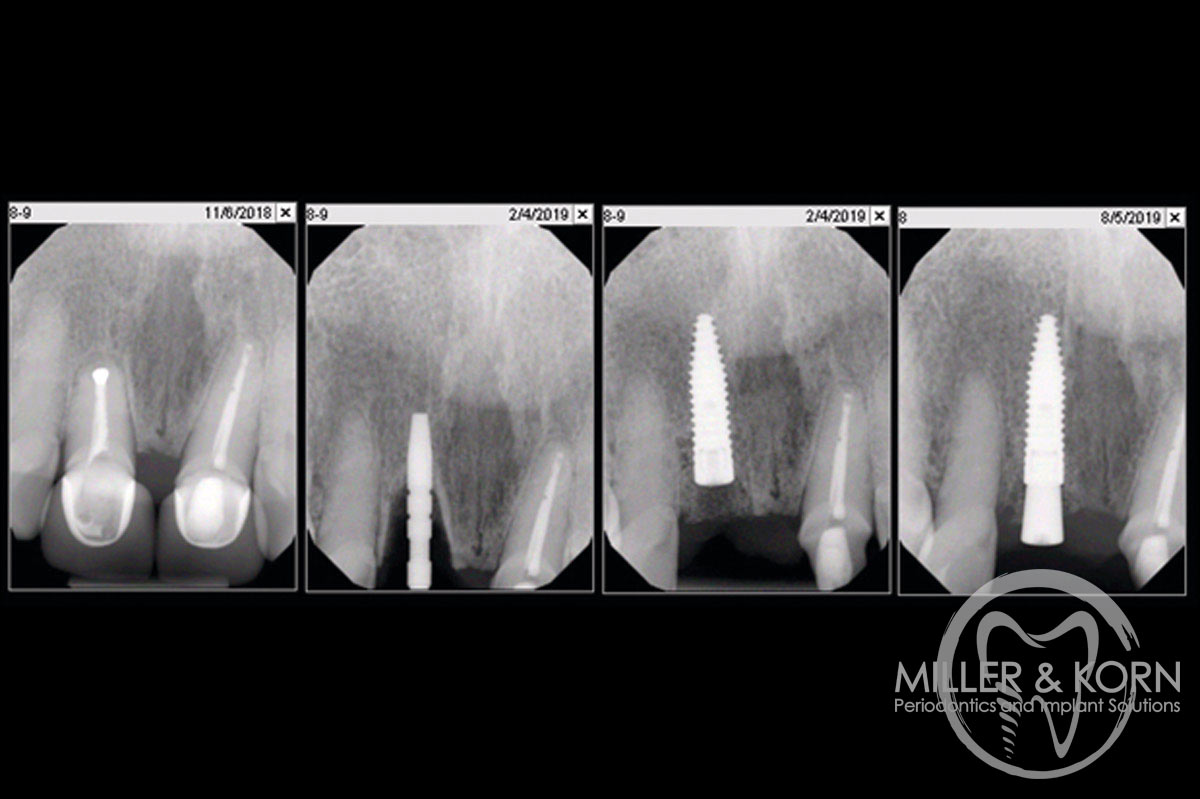

21/22 - Radiographs during therapy.Immediate implant placement and regeneration of ridge using an allograft bone ring and Jason® membrane - Drs. Miller and Korn

22/22 - Final radiograph one week post insertion.Immediate implant placement and regeneration of ridge using an allograft bone ring and Jason® membrane - Drs. Miller and Korn